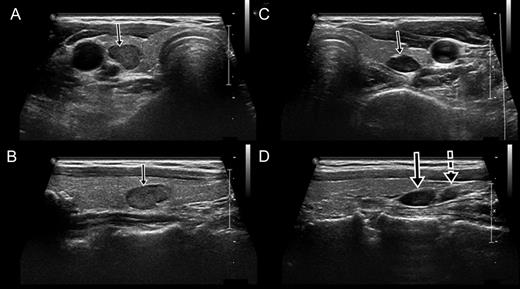

In the preoperative evaluation, two-hour-delayed 99mTc-sestamibi scintigraphy showed increased uptake in both inferior parathyroid glands (Fig. 2). Computed tomography (CT) of the neck showed a calcified nodule posterior to the right superior thyroid gland, a solid nodule in the right lower thyroid gland and an enlarged parathyroid gland posterior to the left inferior thyroid (Fig. 3). Sonography (SONO) showed a benign-looking nodule in the right lower thyroid and two adjoining enlarged parathyroid glands posterior to the left lower thyroid (Fig. 4). The right mid-thyroid nodule appeared benign, and a fine-needle aspiration biopsy was not performed. The right inferior parathyroid gland could not be identified in the CT or SONO findings. During neck exploration, four oval masses similar to parathyroid glands were observed (right superior: 1.7 × 1.0 cm, right inferior: 0.5 × 0.3 cm, left superior: 1.0 × 0.7 cm, left inferior: 0.8 × 0.6 cm). The left inferior parathyroid gland was partially preserved, while the other lesions were completely removed. Intraoperative frozen biopsy of the four masses revealed two cases of parathyroid hyperplasia, a parathyroid hyperplasia with a calcified nodule in the right superior area and a lymph node in the right inferior area. The right inferior parathyroid was not found during right neck exploration.

Sonography showed the right parathyroid gland within the thyroid and the adjoining left parathyroid glands. (A) Transverse view of the right parathyroid gland within the thyroid (arrow). (B) Longitudinal view of the right parathyroid gland (arrow). (C) Transverse view of the left superior parathyroid gland. (D) Longitudinal view of the left superior (arrow) and inferior (dotted arrow) parathyroid glands. The left superior parathyroid had migrated to an inferior position.